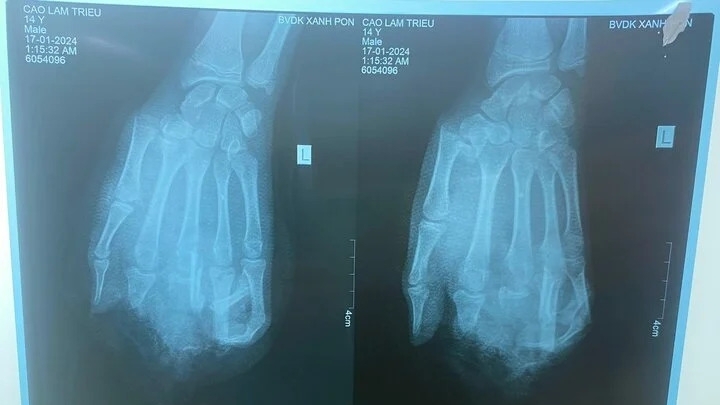

Ngay khi tiếp nhận bệnh nhân, các bác sĩ đã chỉ định phẫu thuật cấp cứu xử trí tổn thương. Do người bệnh bị đa chấn thương, 2 kíp can thiệp được triển khai để tiến hành phẫu thuật cấp cứu xử trí tổn thương cho người bệnh. Hiện sau phẫu thuật, sức khỏe người bệnh ổn định và đang được theo dõi, điều trị tại bệnh viện. Được biết, trong lúc đang lắp bình gas mini để nấu ăn, bất ngờ bình gas phát nổ khiến người đàn ông bị đa chấn thương.